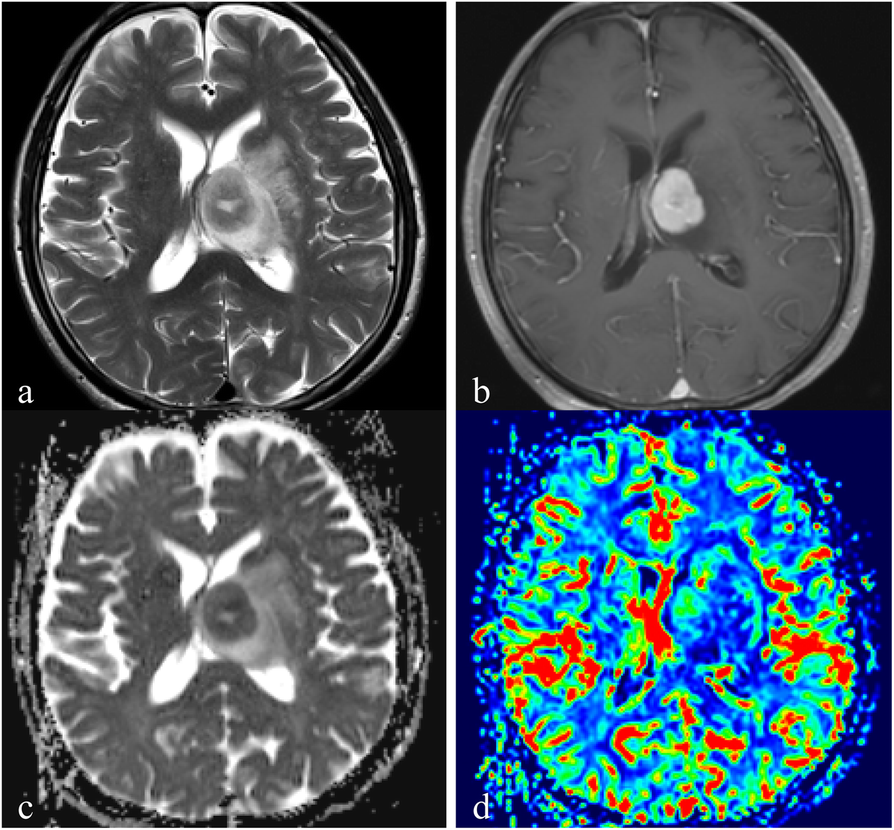

Fig. 4

A 72-year-old man with PCNSLs in the deep gray matter. a. Axial T2WI demonstrates homogeneous high signal intensity on the left basal ganglia region. b. Contrast-enhanced axial T1WI demonstrates a lesion enhancement. c. A corresponding ADC map shows the tumor with a decreased ADC value (ADCmin = 0.49 × 10− 3 mm2/s). The ADCmean value is 0.62 × 10− 3 mm2/s in the right normal deep gray matter. d. A correlative color CBV image shows moderately elevated perfusion with the calculated rCBVmax of 2.10